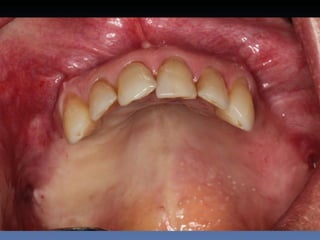

BOX 4

Maurício Zanetti

Idade – 47 anos

Sexo – Masculino

Raça – Caucasiana

ASA – II

Data- 25-04-2012

Diagnóstico: Desdentado parcial

pré-maxila.

Plano de tratamento: Reabilitação pré-maxila com

instalação de 2 implantes endo-ósseos (1.1,.2.2), para

reabilitação protética fixa.